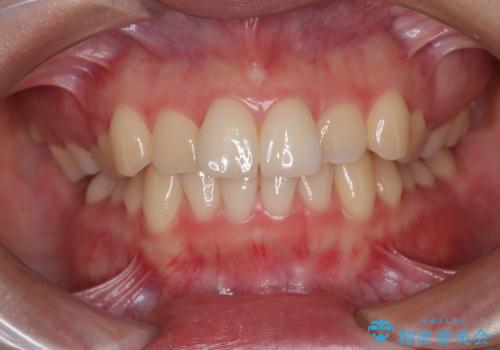

- 上下前歯のデコボコを気にして来院された患者様です。

ワイヤー矯正でもマウスピース矯正でも可能でしたが、短期間で、自身の手を煩わせることなく治療を行いたいとのことで、ワイヤー装置にて矯正治療を行うこととしました。